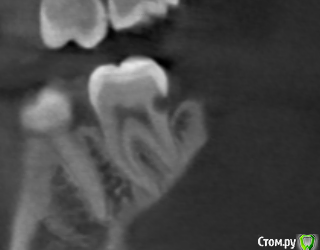

Александр23712 Опубликовано 3 октября, 2020 Поделиться Опубликовано 3 октября, 2020 (изменено) Всем здравствуйте! Я просматриваю частенько вопросы пациентов, ответы на них, недавно была тема вот с таким случаем (см. картинки). Тут вот я и задумался, мы это лечим как обычный второй класс, т.е. доступ с окклюзионной поверхности, сносим все, что выше, и восстанавливаем с помощью Супермата/Тоффльмайера/замковых матриц? При таких концевых дефектах получается и коффер не одеть? В теме был еще вариант про удаление-имплант, но это прям радикально мне кажется. Вот такое должно получиться решение?(картинка 3). Никак не могу смириться с тем, что в некоторых случаях надо иссечь своих тканей столько же, а то и больше, чем сам дефект Изменено 3 октября, 2020 пользователем Александр23712 Ссылка на комментарий